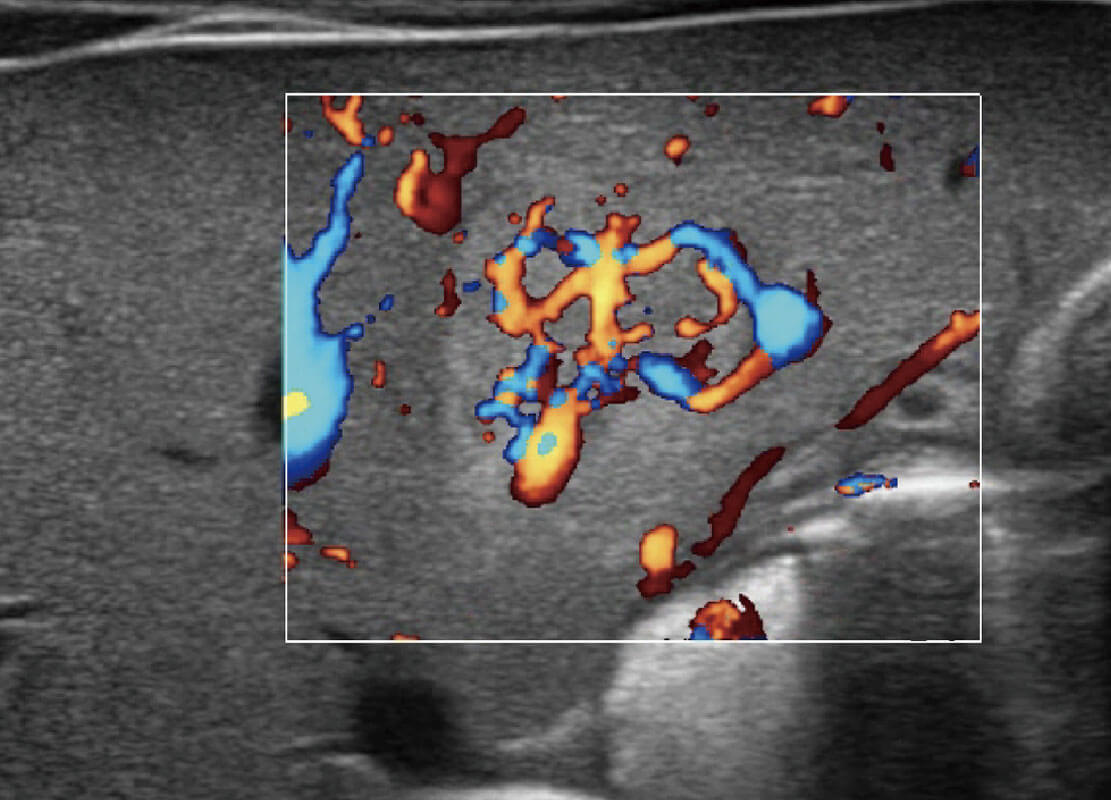

P60优异的图像质量搭载专科探头,在妇科基础疾病的诊断、卵泡生长的监测、输卵管通畅情况的判别等方面为您提供生殖应用方案。

腔内妇科-卵巢

腔内三维-宫内节育器

腔内三维-光影成像